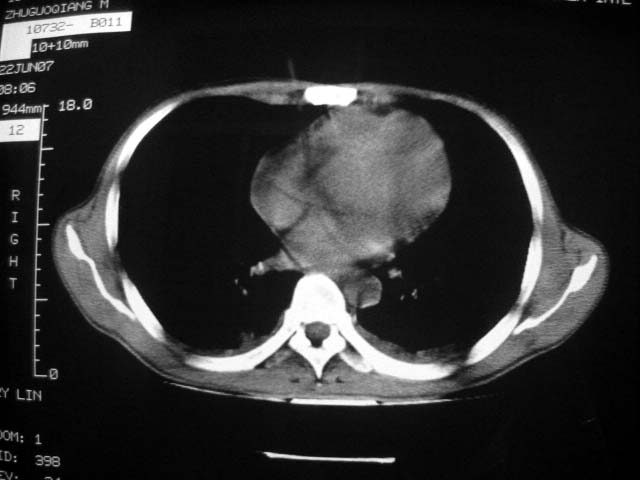

标题: CT7988D:近期图像 出乎意料!

从ct7988c 至今未用任何抗生素及抗痨药,维持保肝治疗。患者低热、咳血渐消失。

07年6月22号复查

前几次大家认为是转移癌,但此次复查病灶却明显吸收好转,不支持诊断。请大家讨论。[emb10]